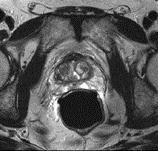

问题 男性,66岁,排尿困难多年,现感会阴部疼痛3个多月,指肛检查触及前列腺表面不规则,行MRI检查,如图所示,你认为最可能的诊断是 ( )

选项 A、前列腺钙化 B、前列腺出血 C、正常前列腺 D、前列腺癌 E、前列腺增生

答案 D